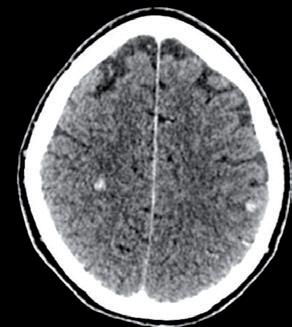

Alla RMN encefalo del 18/02/2022, in sede cerebellare sinistra si conferma la presenza di alterazione sospetta in senso ripetitivo di 15 mm, adesa alla dura madre.

Si evidenzia alterazione osteostrutturale patologica della teca cranica in sede temporo-parietale destra associata a ispessimento lineare della meninge adiacente (figura 3).

3.

TC e RMN encefalo con mdc, febbraio 2022.

Figura